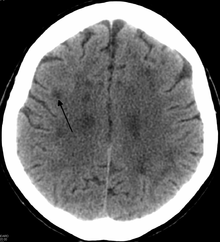

"CT showing a leukoencephalopathy "

An axial CT scan of a patient presenting a leukoencephalopathy, the base disorder to the family of disorders that HDLS falls under.

In HDLS, there is enlargement of the lateral ventricles and marked thinning or weakening of cerebral white matter.[9] The loss of white matter is caused by myelin loss. These changes are associated with diffuse gliosis, moderate loss of axons and many axonal spheroids.[1]